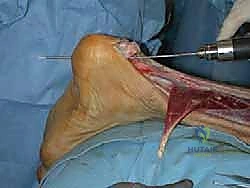

- FHL Tendon Harvest:

- Technique: With the ankle and hallux held in full flexion, apply maximum traction to the FHL tendon. Then, transect the tendon as distally as possible, typically at the level of the medial malleolus or even more distally.

- Surgical Pearl: Maximizing traction and cutting distally ensures you obtain adequate tendon length for transfer, which is crucial for a tension-free augmentation. In almost all cases, this technique yields sufficient length.

TECH FIG 4 • C. The FHL tendon is transected at the medial malleolar level, leaving adequate tendon length for the transfer.